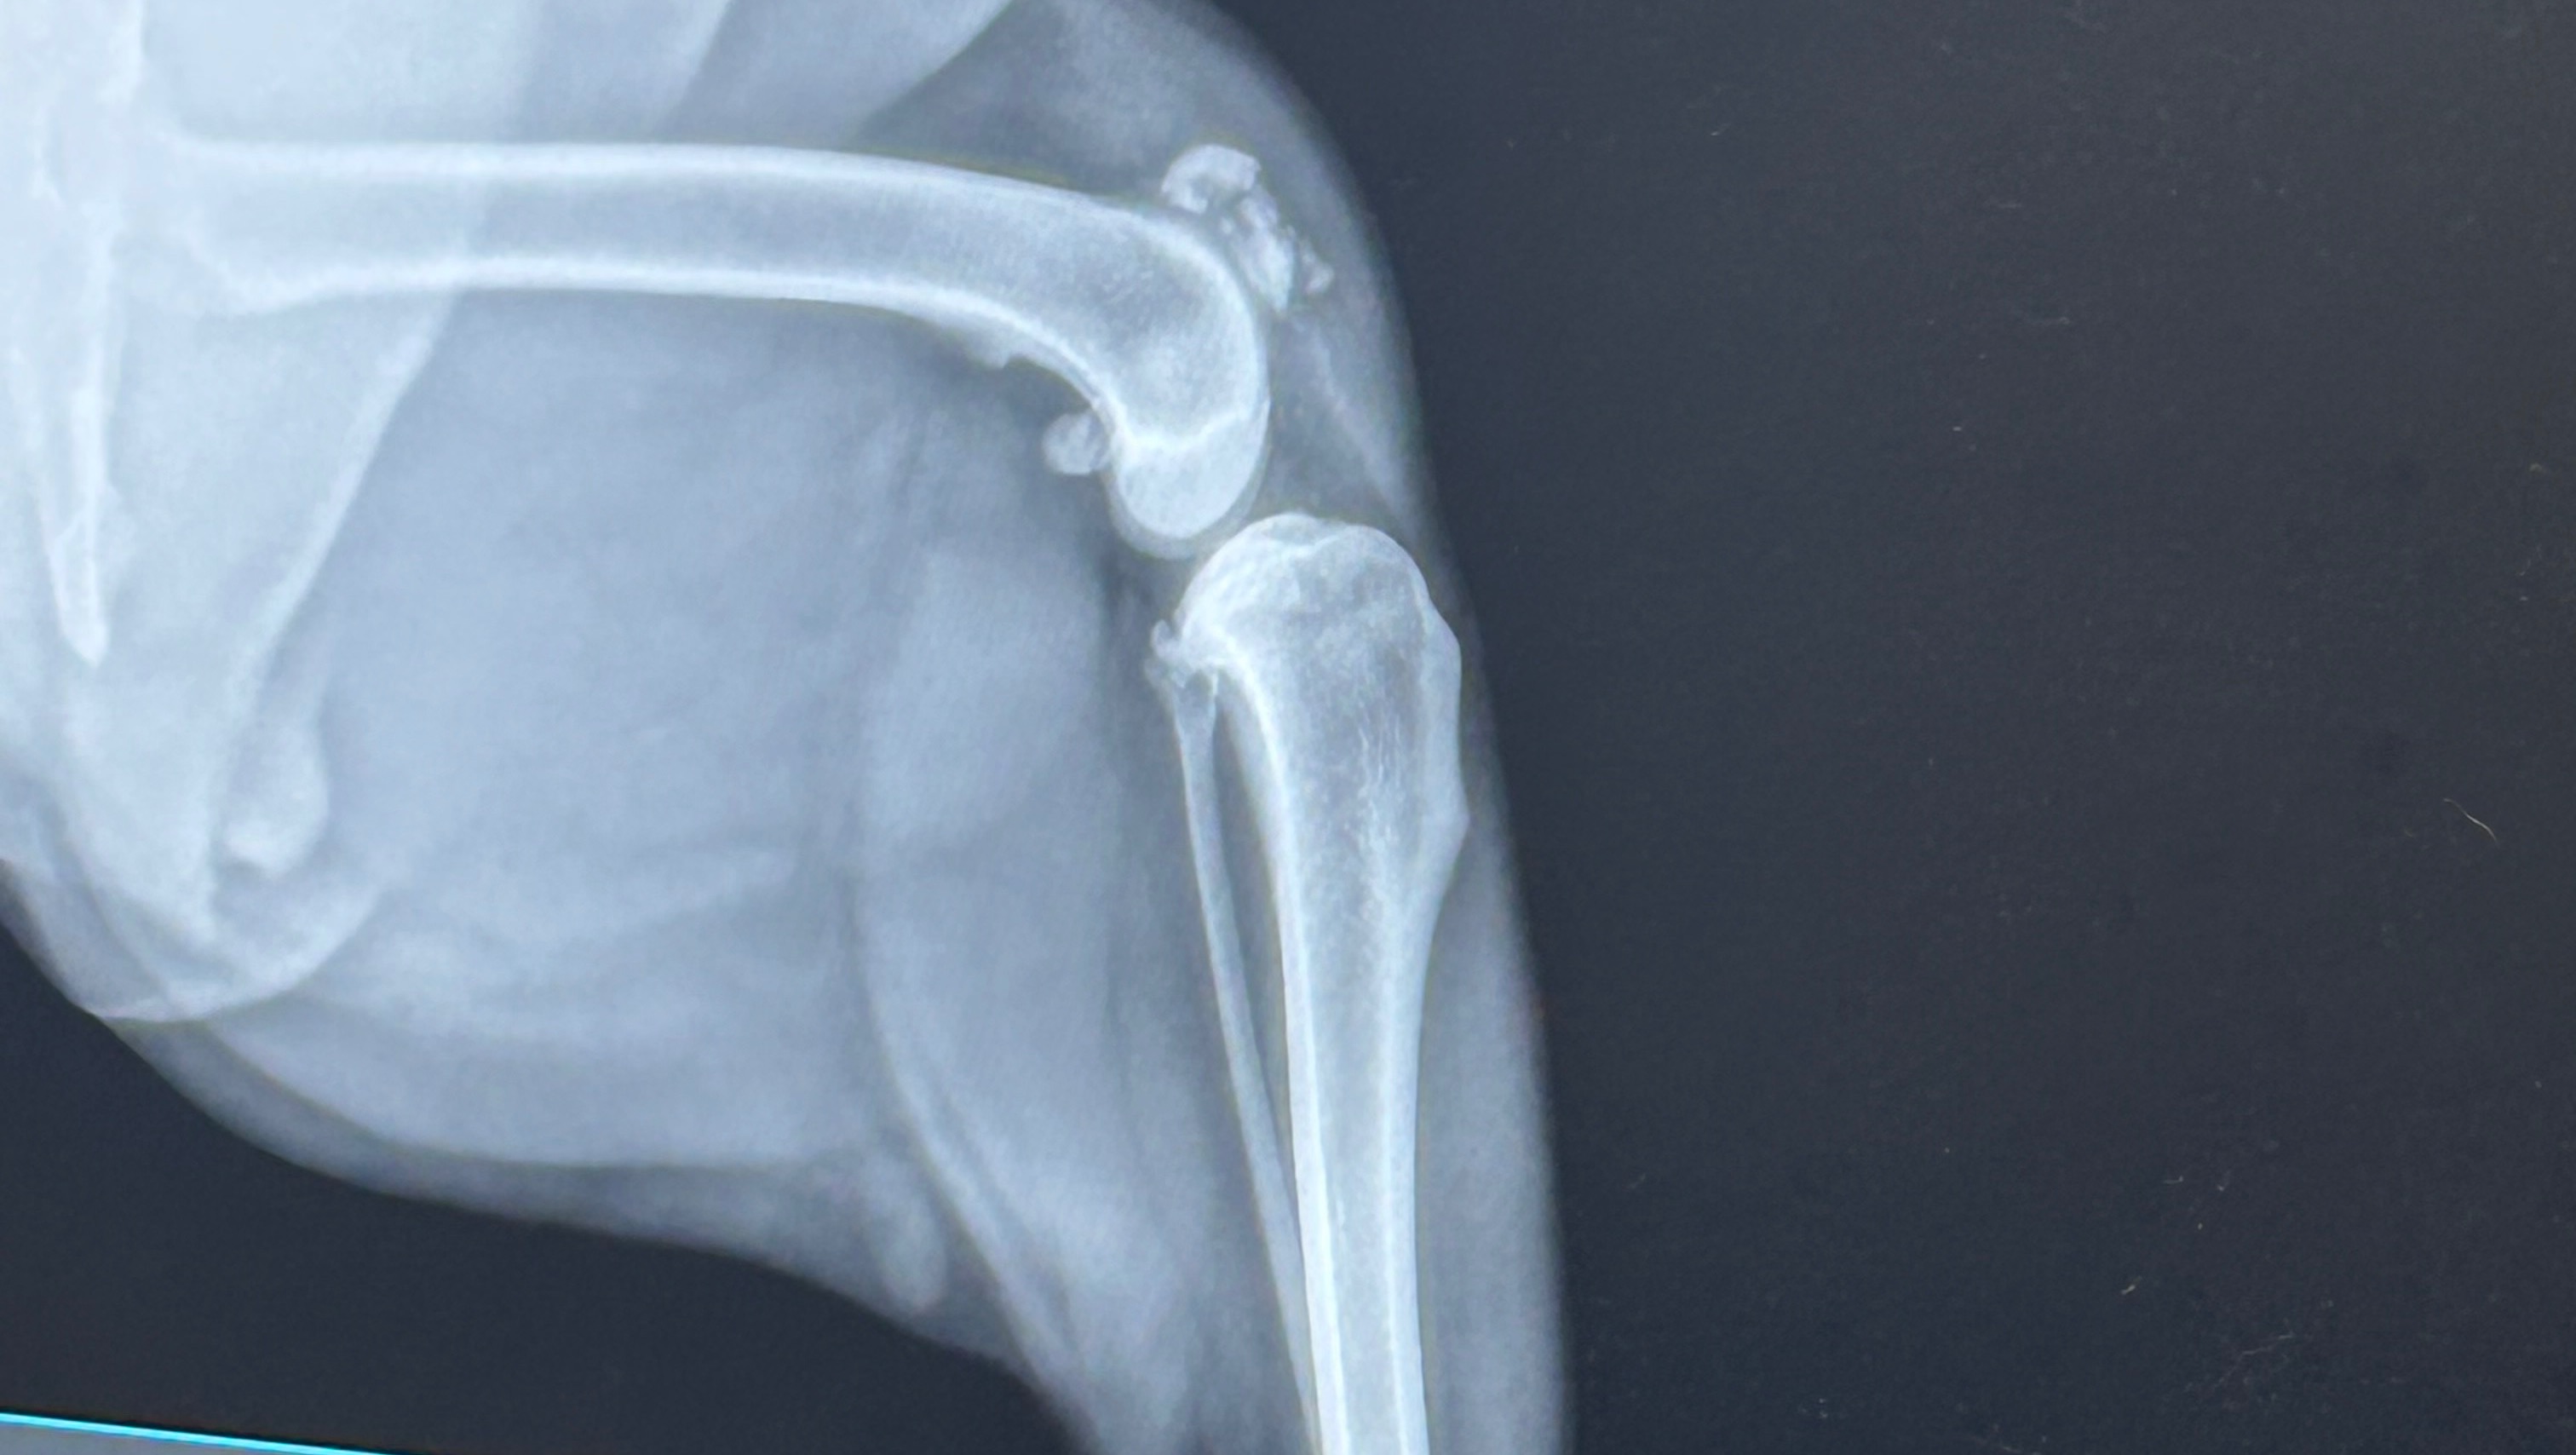

Ami is my 4 year old pit bull blue heeler who I love with my whole world but unfortunately on 3-9-25 she decided to jump out of our car window and shattered her Patella and had to go into emergency surgery to attempt to fix her shatter, Luckily UC Davis was successful with her surgery and placed a External Fixator on her knee, Ami is going to need weekly appointment and check ups for the next 12 weeks, Her total amount was 6,600$ and fortunately my boyfriend and I got accepted for CareCredit to help out with her emergency surgery, But this bill is going to be a hardship on me and my boyfriend for a while but it’s do-able but it would be even more helpful if we could get any help at all even a share helps during this hardship for my little family and I, thank you for reading this and taking your time to share I appreciate you guys more then anything